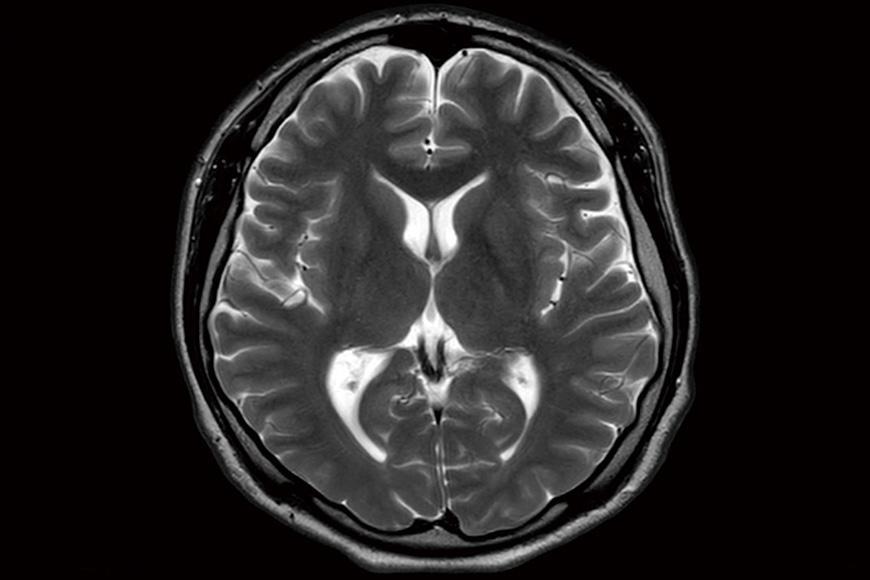

MRI(磁気共鳴画像)・MRA(磁気共鳴血管撮影法)・頸動脈超音波・身体計測・血液検査・尿検査